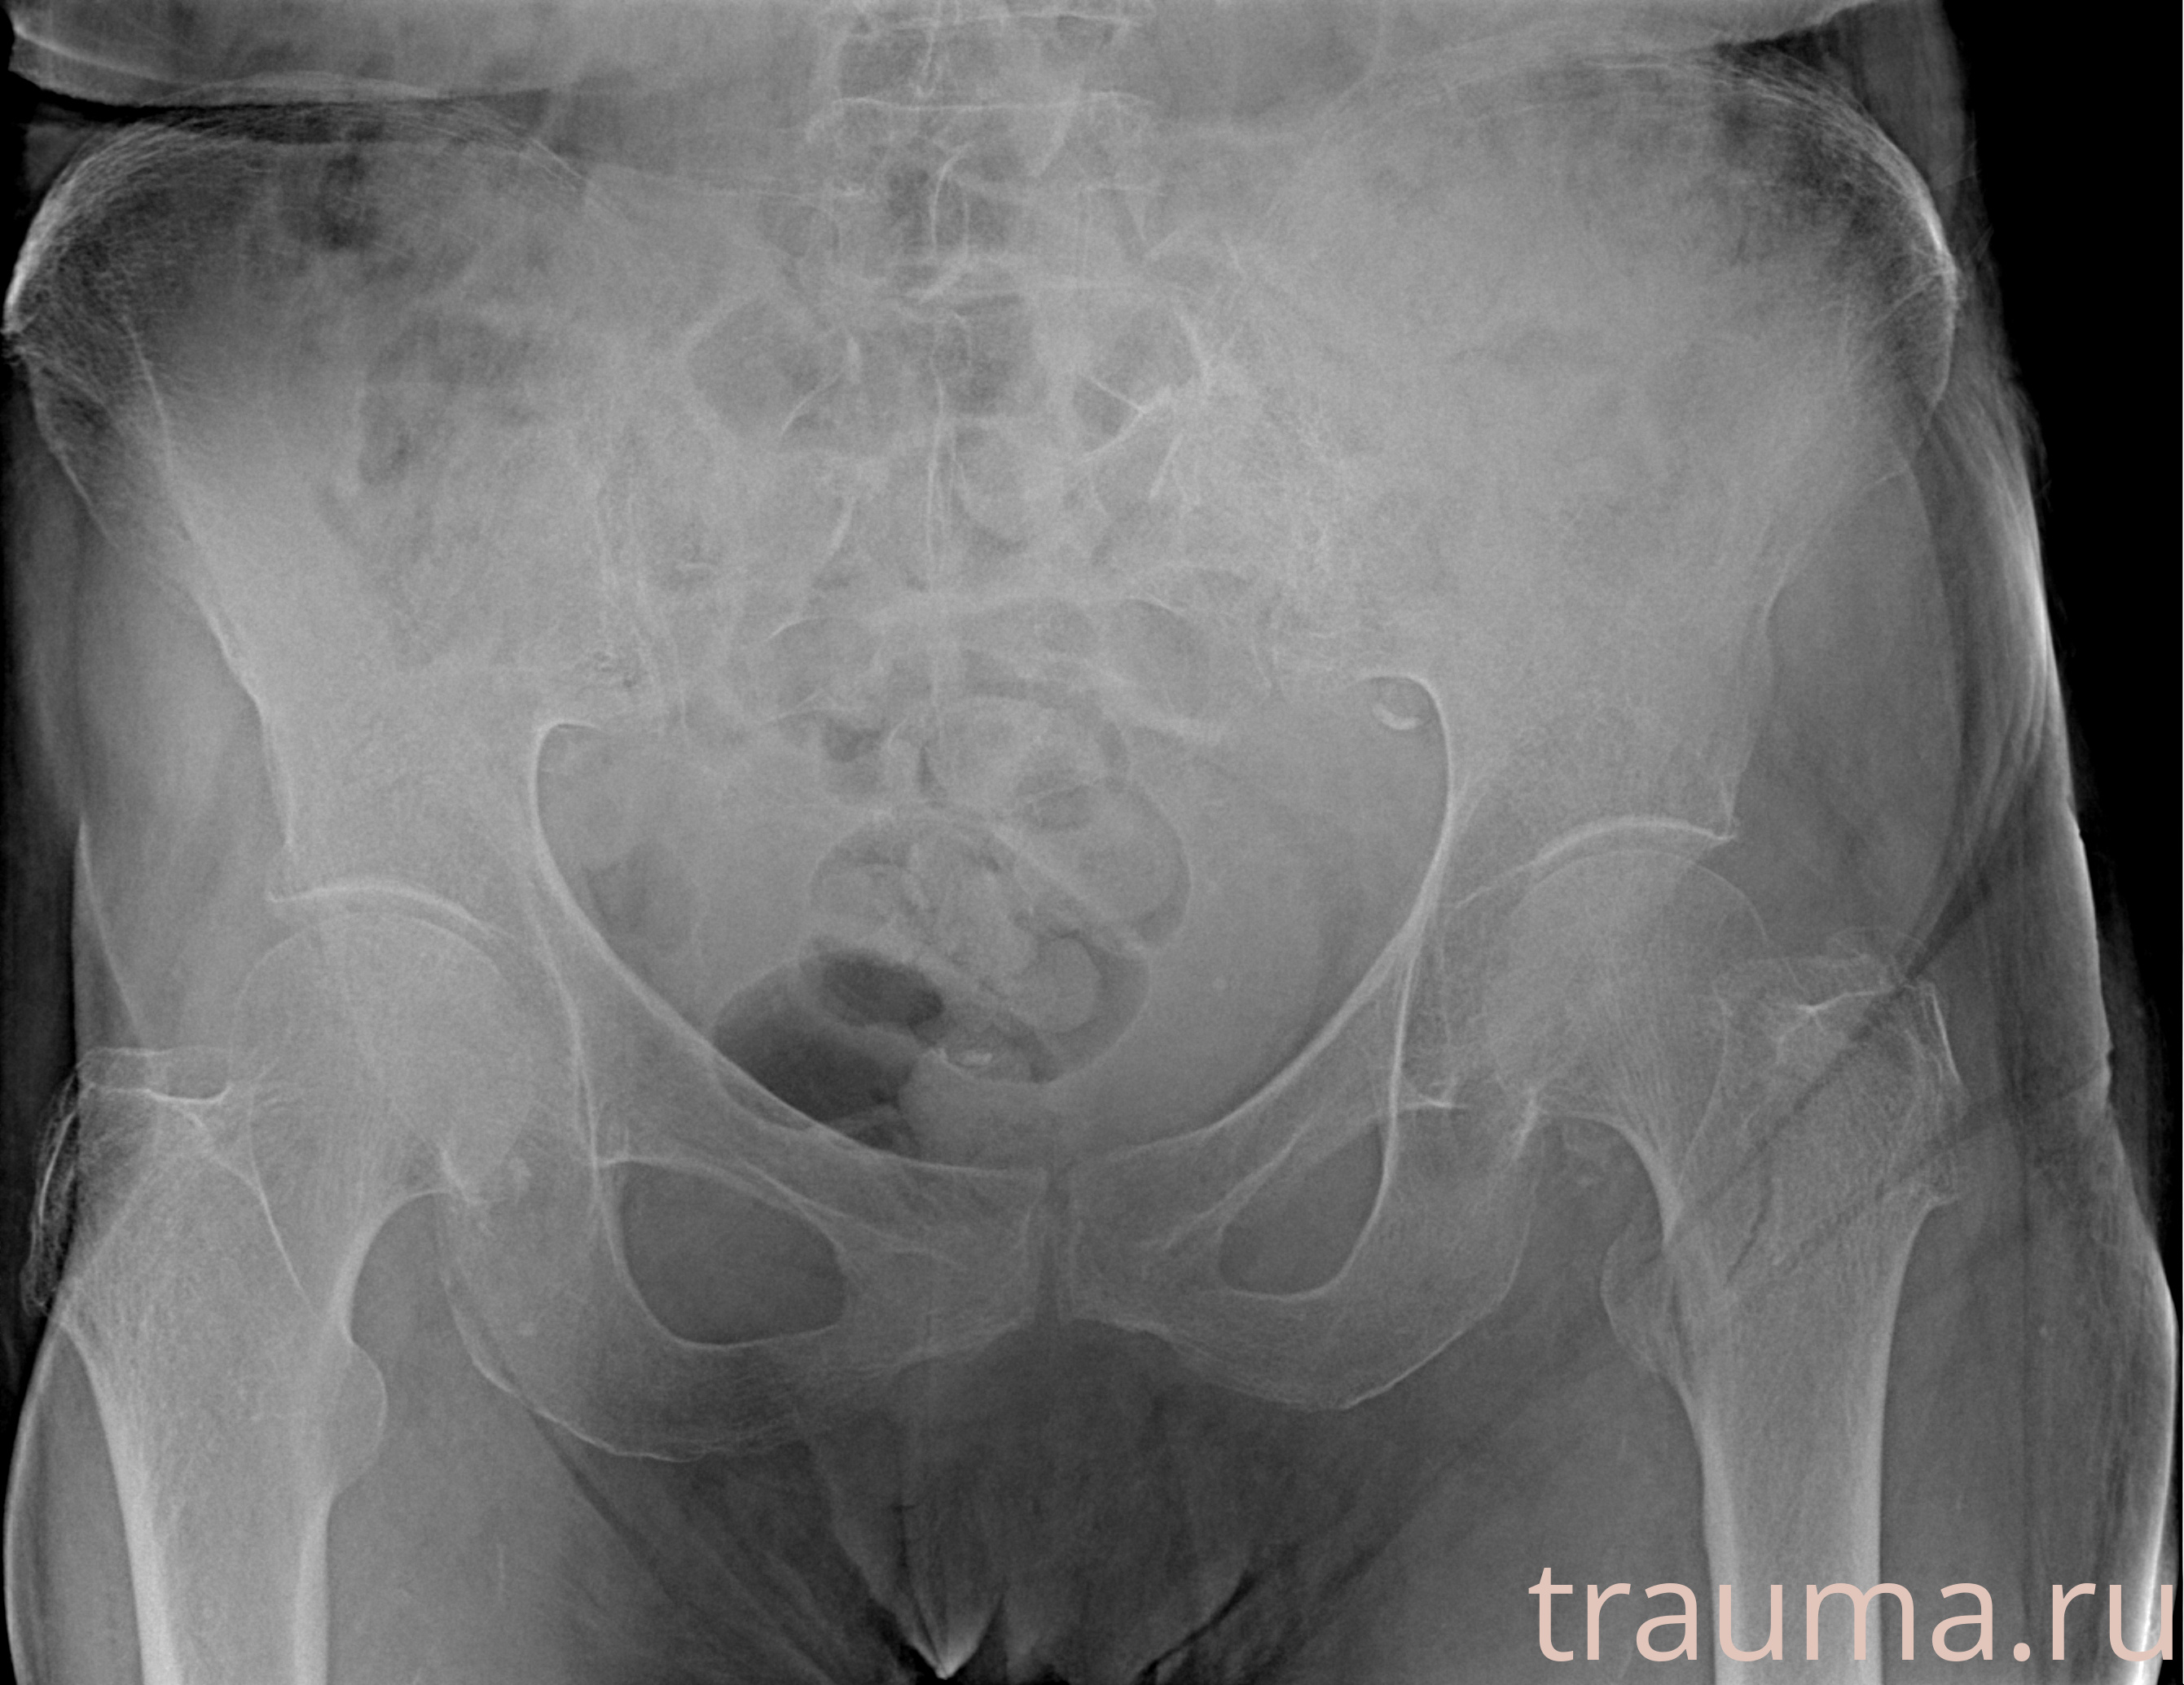

Рентгенограммы

Рентген на дому: по вашему адресу приезжает врач-рентгенолог, травматолог-ортопед с мобильным рентгеновским аппаратом, проводит диагностику травмы или заболевания, делает необходимые рентгенограммы, дает рекомендации по дальнейшему лечению. Получить качественные снимки в домашних условиях возможно благодаря уникальной методике, разработанной МосРентген Центром для института  Склифосовского

при переломе шейки бедра и пневмонии от компании МосРентген Центр - партнера Института имени Склифосовского